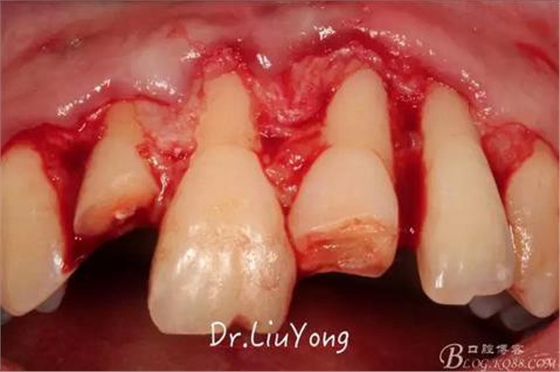

系帶手術后兩周,進行上頜前牙唇側的牙齦退縮的手術治療,由于局部附著齦缺如及牙齦厚度不足,因此同期進行上皮下結締組織移植,解決附著齦及牙齦厚度不足的問題。

術中,可見明顯的唇側骨開裂,如上圖